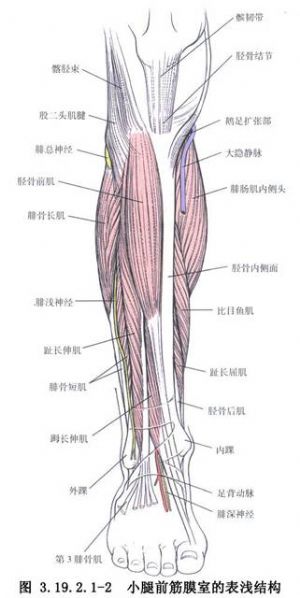

雙側貼附植骨術用於先天性脛骨假關節的手術治療。雙側貼附植骨術爲Boyd所創用。他認爲雙側皮質骨固定比較結實,對線好,可保持脛骨乾的足夠寬度,還可防止瘢痕壓迫植入的松質骨。如果一側植骨塊被吸收,其對側植骨塊仍存在,再骨折的可能性少,治癒率較高(圖3.19.2.1-1)。但該法對較低位脛骨假關節的遠端植骨片固定有一定難度。Tachdjian改良了Boyd手術,除雙側貼附植骨外,改用加壓器固定或斯氏針髓內固定,此法除解決了較低位脛骨假關節的固定問題,尚可促進骨癒合。手術相關解剖見下圖(圖3.19.2.1-2,3.19.2.1-3)。